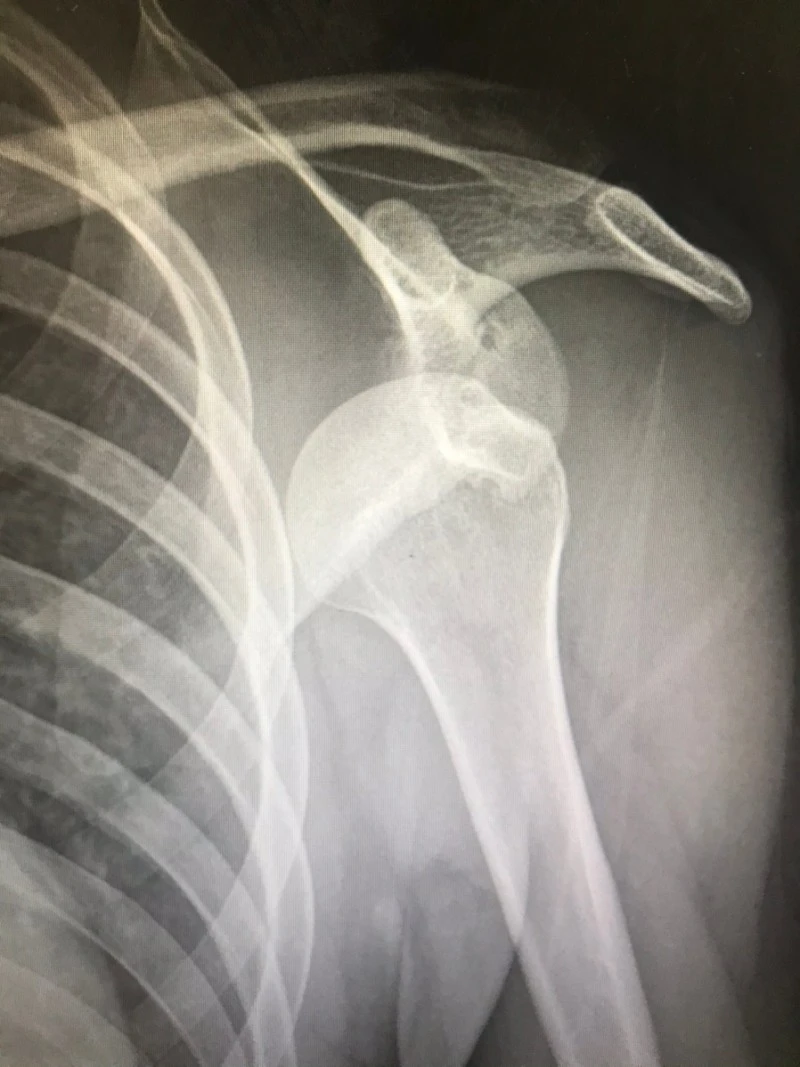

유쾌하고 출근해서 상쾌하게 진료하는데, 스무 살 청년이 축 처진 어깨를 붙잡고 응급실에 들어왔어요. 통증의 극심함이 관상에 온전히 드러납니다. 습관성 어깨 탈구로 수술도 받았고, 2주 전에도 재발하여 견인 치료를 받았다네요. 내원 40분 전에 운동하며 왼팔에 힘을 주다가 다시 어깨가 궤도를 이탈했답니다.

아파서 눕지도 못하길래 진통제부터 투여했고요. 통증은 진정되었으나 겁기劫氣는 증폭된 청년의 팔을 붙잡고 어깨 컴백홈 시술을 시행했습니다. 짧고 굵은 비명과 함께 청년의 윗팔뼈는 본연의 위치로 복귀했고요. 식은땀 지옥에 다녀온 청년에게 암슬링(arm sling) 장착하였습니다.

제가 주로 애용하는 방법으로 정복했는데, 그 청년이 그러네요. 여지껏 여러 번 시술을 받았는데 가장 신박했다고. 다음 단계의 테크닉 쓰기 전에 정복이 잘 되어 다행이라고 내심 생각했습니다. 롤러코스터가 읊조린 바대로 습관이란 게 무서운 겁니다만, 학생과 저 다시 보진 말기로 해요. 지긋지긋한 탈구에서 완전히 탈출한, 신박한 여생이길 염원합니다.